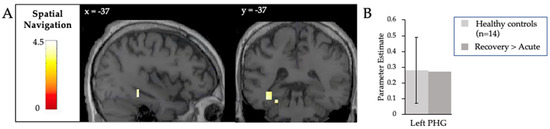

3.2. Command Following

| Spatial Navigation | Left parahippocampal gyrus | −37, −37, −25 | 4 | 3.96 |

| Left parahippocampal gyrus | −27, −37, −15 | 2 | 3.68 |